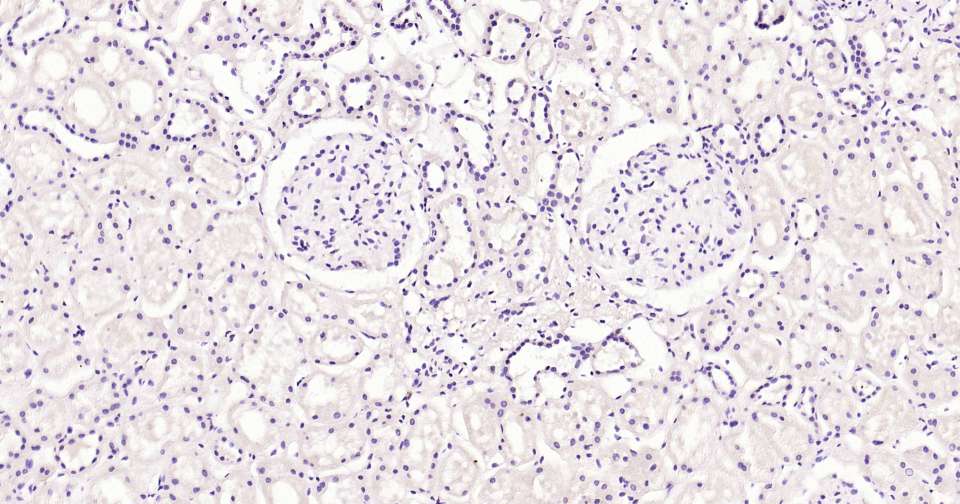

Immunohistochemical analysis of paraffin embedded human kidney tissue slide using IHC0386H (Human BLBP Kit).